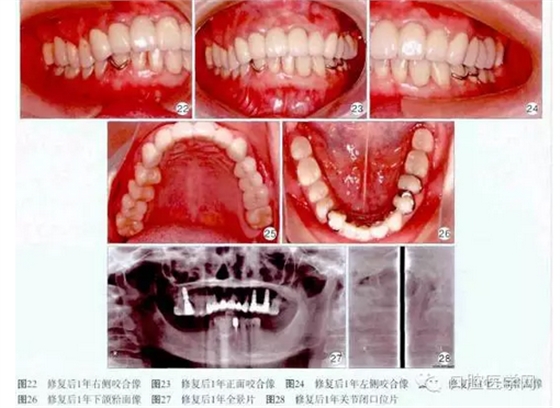

1個月后用Fuji玻璃離子水門汀(GC公司,曰本)永久粘固上頜烤瓷冠撟。修復(fù)后1年復(fù)查,患者訴義齒咀嚼、發(fā)音功能良好,舒適美觀,無壓痛。檢查:口腔衛(wèi)生良好,牙齦正常,種植體穩(wěn)固,咬合良好(圖22~26)。X線片示:16、24、26種植體頸部無明顯骨吸收,顳下頜關(guān)節(jié)維持原有狀態(tài)(圖27~28)。